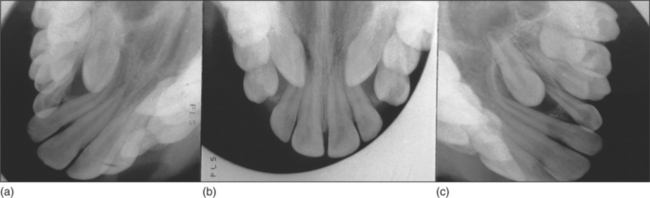

The main methods of localization are (1) use of parallax or (2) two films taken at right angles to one another. Parallax movement can be assessed in both the horizontal and vertical planes by taking two periapicals with differing X-ray tube angles or an anterior and an oblique occlusal view (Fig. 5.22). If the unerupted tooth appears to move in the same direction as the X-ray tube, then it is lying palatally. A panoramic radiograph plus an anterior occlusal or lateral skull radiograph may also be used. A vertex occlusal view is best avoided, as it requires a large dose.

image

Fig. 5.22 Use of (a, c) oblique maxillary occlusal and (b) anterior maxillary occlusal views to identify palatal positioning of upper left and upper right canines by parallax. See text for detail.